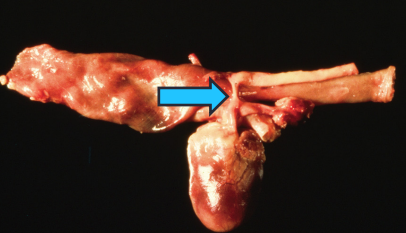

Persistent Right Aortic Arch

Et: vascular ring traps esophagus, constriction near heart base

Sig: Young <6m, onset at weaning

Cs: regurg.

solids > liquids

Dt: thoracic rads, contrast esophagram or CT

Tx: Sx

Comp: residual dilation when delayed